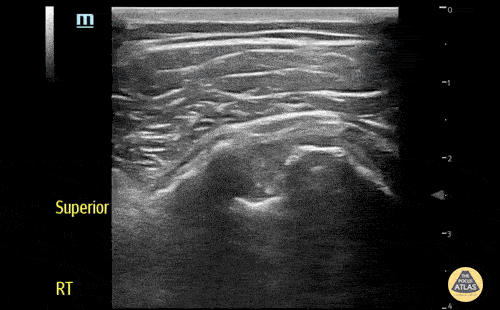

Musculoskeletal - Biceps long head tendon rupture, transverse view

The patient presented with sudden onset right shoulder pain. On physical examination, there was tenderness to palpation anteriorly over the humeral head. POCUS demonstrated a heterogeneous structure within the bicipital groove representing a tendon stump surrounded by a developing anechoic haematoma. This study is in keeping with a complete rupture of the biceps long head tendon. This case illustrates the utility of POCUS as a diagnostic tool for the rapid identification of MSK injuries in the ED. Contributors: Andrew Namespetra(@AndrewNamespet1), MB BCh BAO MSc; Nava Kendall, MD